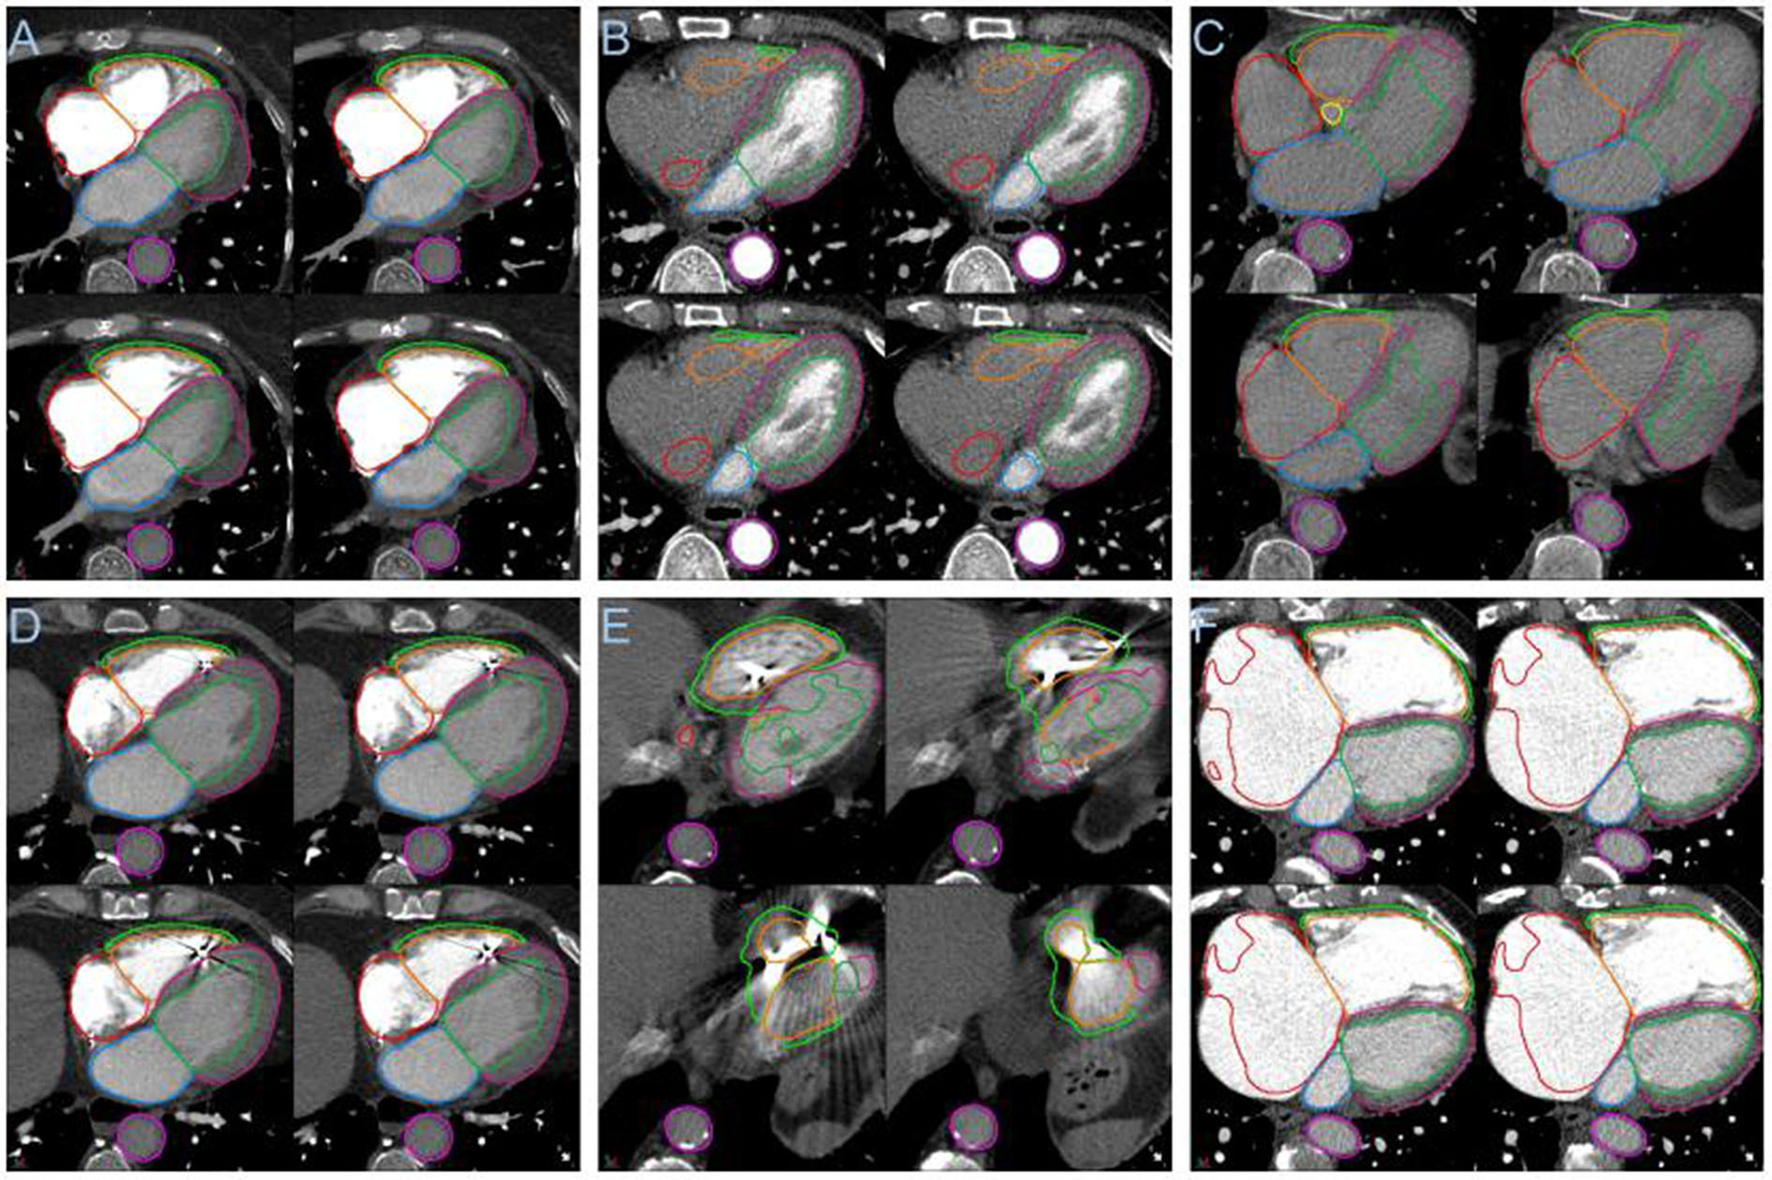

In the large PH and PE cohorts the failure rate was low, <3.9% for failure of any structure. The pathologies causing failures were pericardial effusions see Figure 8A, the poor differentiation of effusion and LV myocardium primarily led to LV epicardial contour failure. Poor contrast opacification was a major cause of failure, see Figures 8B,C. The segmentation performance may be improved by including additional patients with very poor contrast in the training dataset, or alternatively a method for identifying poor opacification prior to automated segmentation may be desirable, as it may not be appropriate to analyse such cases. The model generally performed well in patients with intracardiac devices such as pacemakers, see Figure 8D. Though failures in such cases were identified, see Figure 8E. Local and global chamber dilatation was thought to be the cause for several failures, see Figure 8F, and the addition of more extreme data to the training cohort may improve the performance of the DL model in these cases.

Figure 8

(A) Segmentation failure in the LV myocardium in the presence of pericardial effusion. (B) Failure of segmentation of right sided cardiac structures with poor right sided contrast opacification. (C) Segmentation failure apically with globally poor contrast opacification. (D) Example showing success in the presence of an intracardiac device. (E) Segmentation failure in the region of an intracardiac device. (F) Failure in right atrial segmentation with severe dilatation.